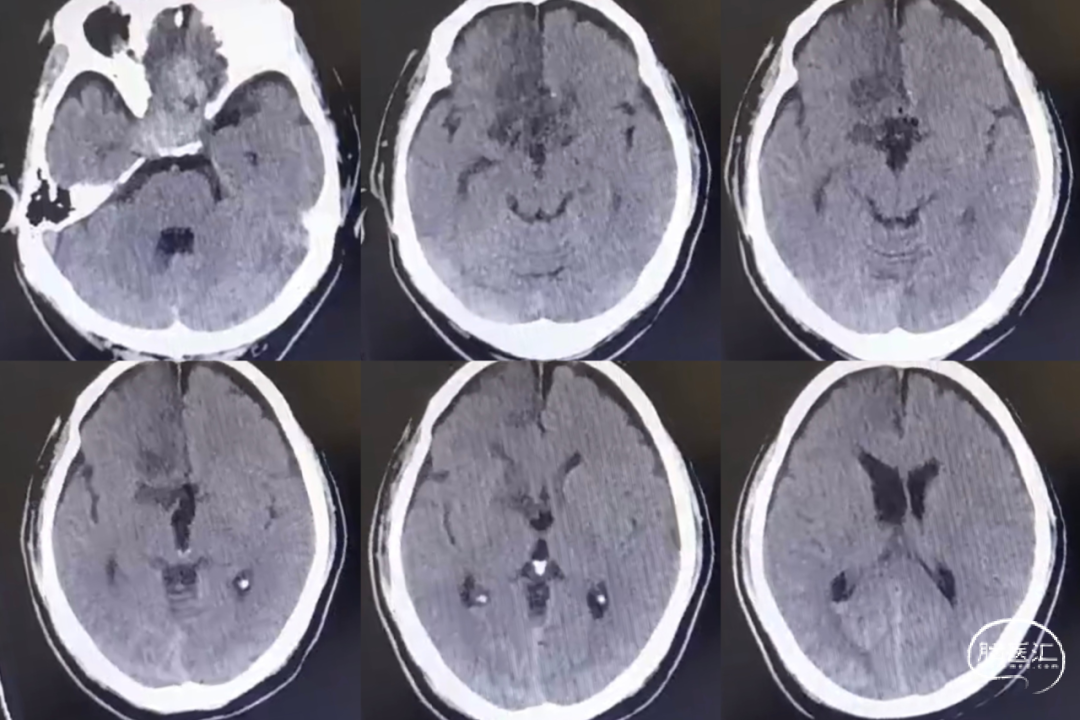

术后1周头颅CT

术后患者恢复良好。无脑脊液鼻漏及颅内感染;术后视力同术前。